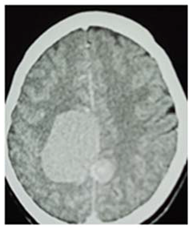

# Case 6

This 40 years middle age man, worker, experienced history of convulsions, mood change and visual hallucinations over 6 months duration, few day before his presentation, he developed Lt side weakness.

Before surgery, we speak to the patient himself and his family clearly, regarding the complication of surgery and the tumor prognosis.

Operation: Patient was prepared for surgery, and through Rt posterior parietal craniotomy it was found that, highly vascular tumor, with thromboses blood vessels, nearly macroscopic total excision was completed.

Patient was recovered from anesthesia and taken to the ICU

Histopathology

Shows GBM, and eventually the patient was planned for adjuvant therapy, chemotherapy and radiotherapy and eventually sent to Merowe town isotope center.